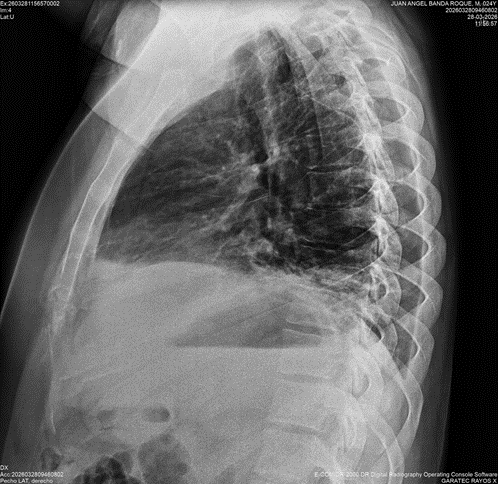

Le solicito una Radiografia y confirmo mi diagnostico. La Radiografia muestra el infiltrado basal pulmonar y pleurits basal derecha, compatible con Neumonía Lipoidea exógena.

El hallazgo característico en CT es que se registran en las áreas inflamadas de predominio basal UH de -30 a – 150

Los patrones en CT son : Areas de consolidación. Patron en vidrio deslustrado. Patron intersticial en empedrado ( crazy-paving ) superpuesto al patron de vidrio deslustrado. Nódulos o masas de bordes irregulares ( algunos de ellos pueden mostrar habitación ) y pueden ser confundidos con Ca pulmonar.